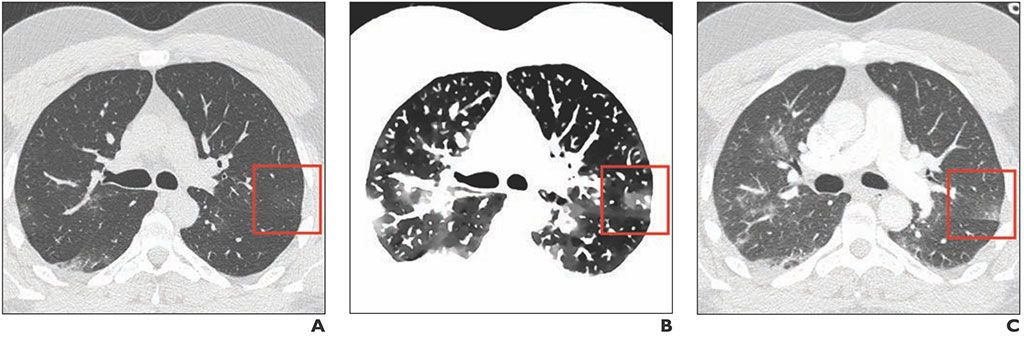

Imagen: Imagen de TC axial convencional inicial (A), imagen DE espectral que muestra claramente las lesiones GGO e imagen de TC axial convencional dos días después de las imágenes A y B (C). (Fotografía cortesía del AJR)

Un estudio nuevo sugiere que el uso de TC espectral con imágenes de densidad electrónica (DE) puede indicar el grado de opacidad pulmonar en vidrio esmerilado (GGO, por sus siglas en inglés) en pacientes con COVID-19 con enfermedad en estadio temprano.

Las 45 GGO identificadas en los cuatro pacientes se mostraron mejor en las imágenes DE que en las tomografías computarizadas iniciales convencionales, y las tomografías computarizadas convencionales de seguimiento confirmaron la presencia de las GGO. Además, los resultados mostraron que la extensión de la lesión, evaluada mediante una escala de informe semicuantitativa que denota la afectación del área de superficie para cada lóbulo, era mucho más fácil de determinar en las imágenes DE. El estudio fue publicado el 21 de octubre de 2020 en la revista American Journal of Roentgenology.